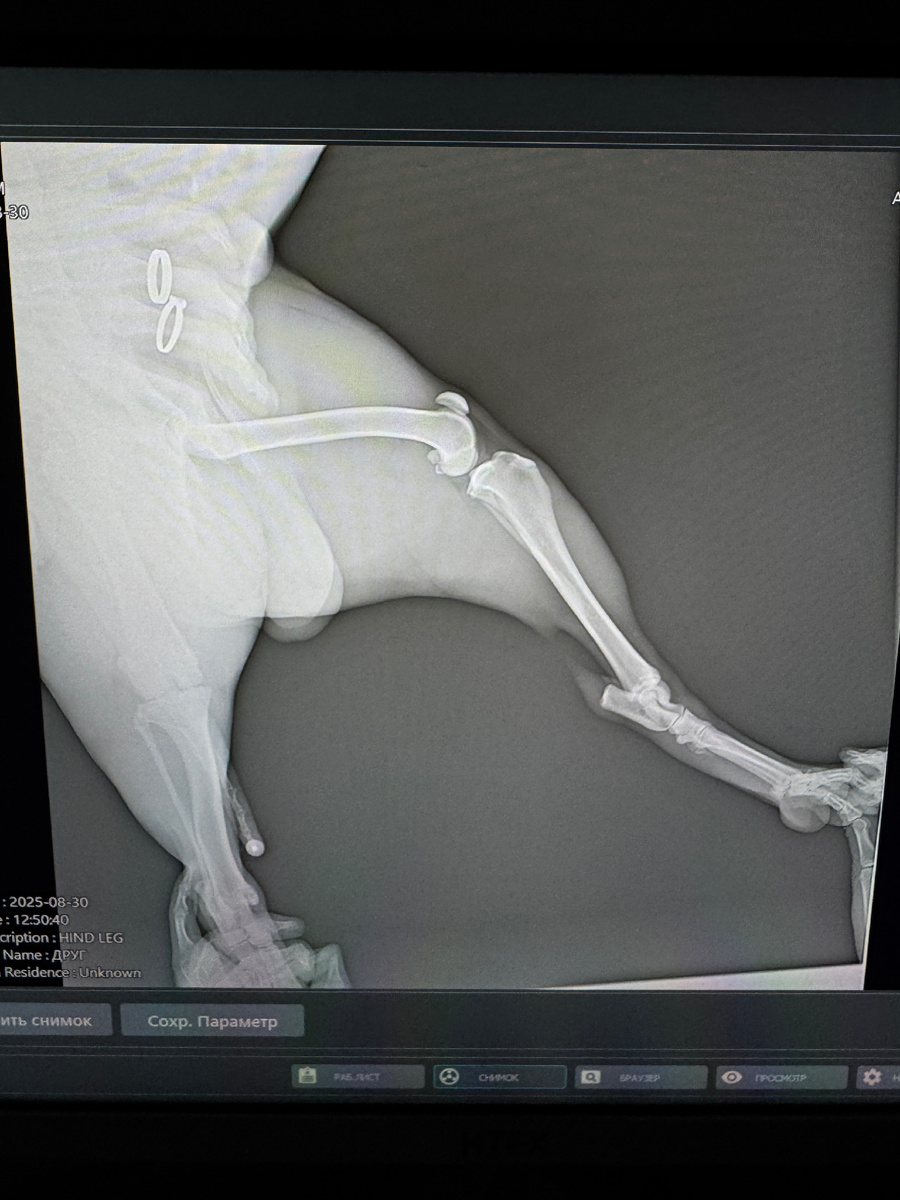

Первый раз мы приехали туда, когда Том внезапно начал хромать. Я сильно перепугался: до этого его укусил клещ, и мы думали, что это связано. В клинике сделали полный осмотр, рентген, назначили лечение — и через неделю всё прошло.